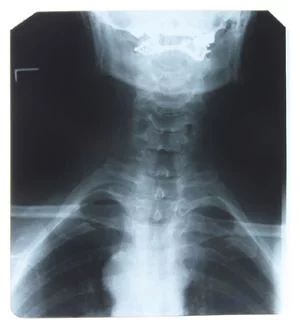

Podczas sekcji zwłok i badań tomograficznych specjaliści stwierdzili u generała m.in.: złamania w obrębie lewego oczodołu i po lewej stronie kości czołowej wraz z zatoką, liczne obustronne złamania żeber - niektórych w kilku miejscach, złamanie końca barkowego prawego obojczyka, złamania poprzecznych wyrostków w odcinku lędźwiowym kręgosłupa, dwa złamania kości łokciowej prawej ręki, spiralne złamanie prawej nogi oraz kości piętowej. Kość gnykowa była nieuszkodzona. Ze względu na rozkład zwłok medycy nie mogli zbadać organów wewnętrznych.

Antropolodzy stwierdzili, że badany szkielet należał do mężczyzny popularnego w Polsce typu subnordycznego, który miał 52,5-62 lata i ok. 171 cm wzrostu. Na podstawie tomografii komputerowej wykonano rekonstrukcję wyglądu czaszki. Podczas badań w Zakładzie Diagnostyki Obrazowej Szpitala Uniwersyteckiego w Krakowie wykonano zdjęcia rentgenowskie całej sylwetki generała oraz komputerowe badanie tomograficzne, dzięki czemu uzyskano ok. 2 tys. obrazów poprzecznych przekrojów ciała, które posłużyły do późniejszych rekonstrukcji.